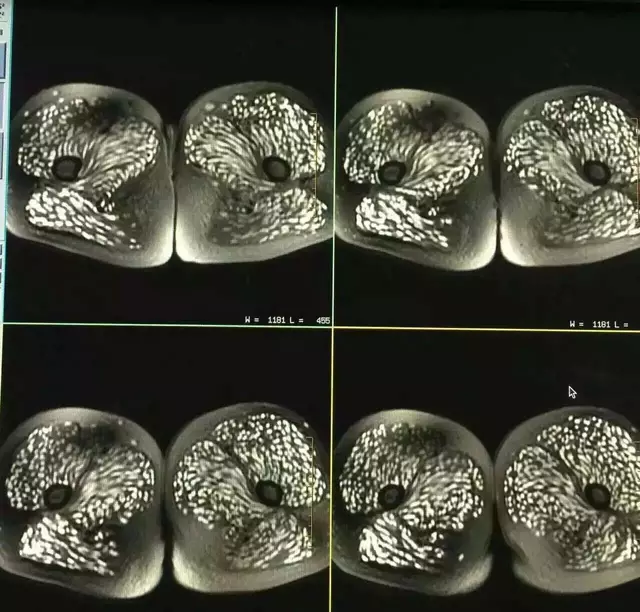

The images suggested cysticercosis, a serious infection that develops when a person swallows tapeworm eggs. Instead of staying in one place, the parasites can travel through the body. In Tingting’s case, doctors believed they had spread into her back muscles, abdomen, eyes, and brain.

Soon, her family history offered a clue. On days the family slaughtered a pig, they often ate the meat raw. Tingting had kept that tradition for years, starting in her teens. Her brother also received testing, but he did not show infection.